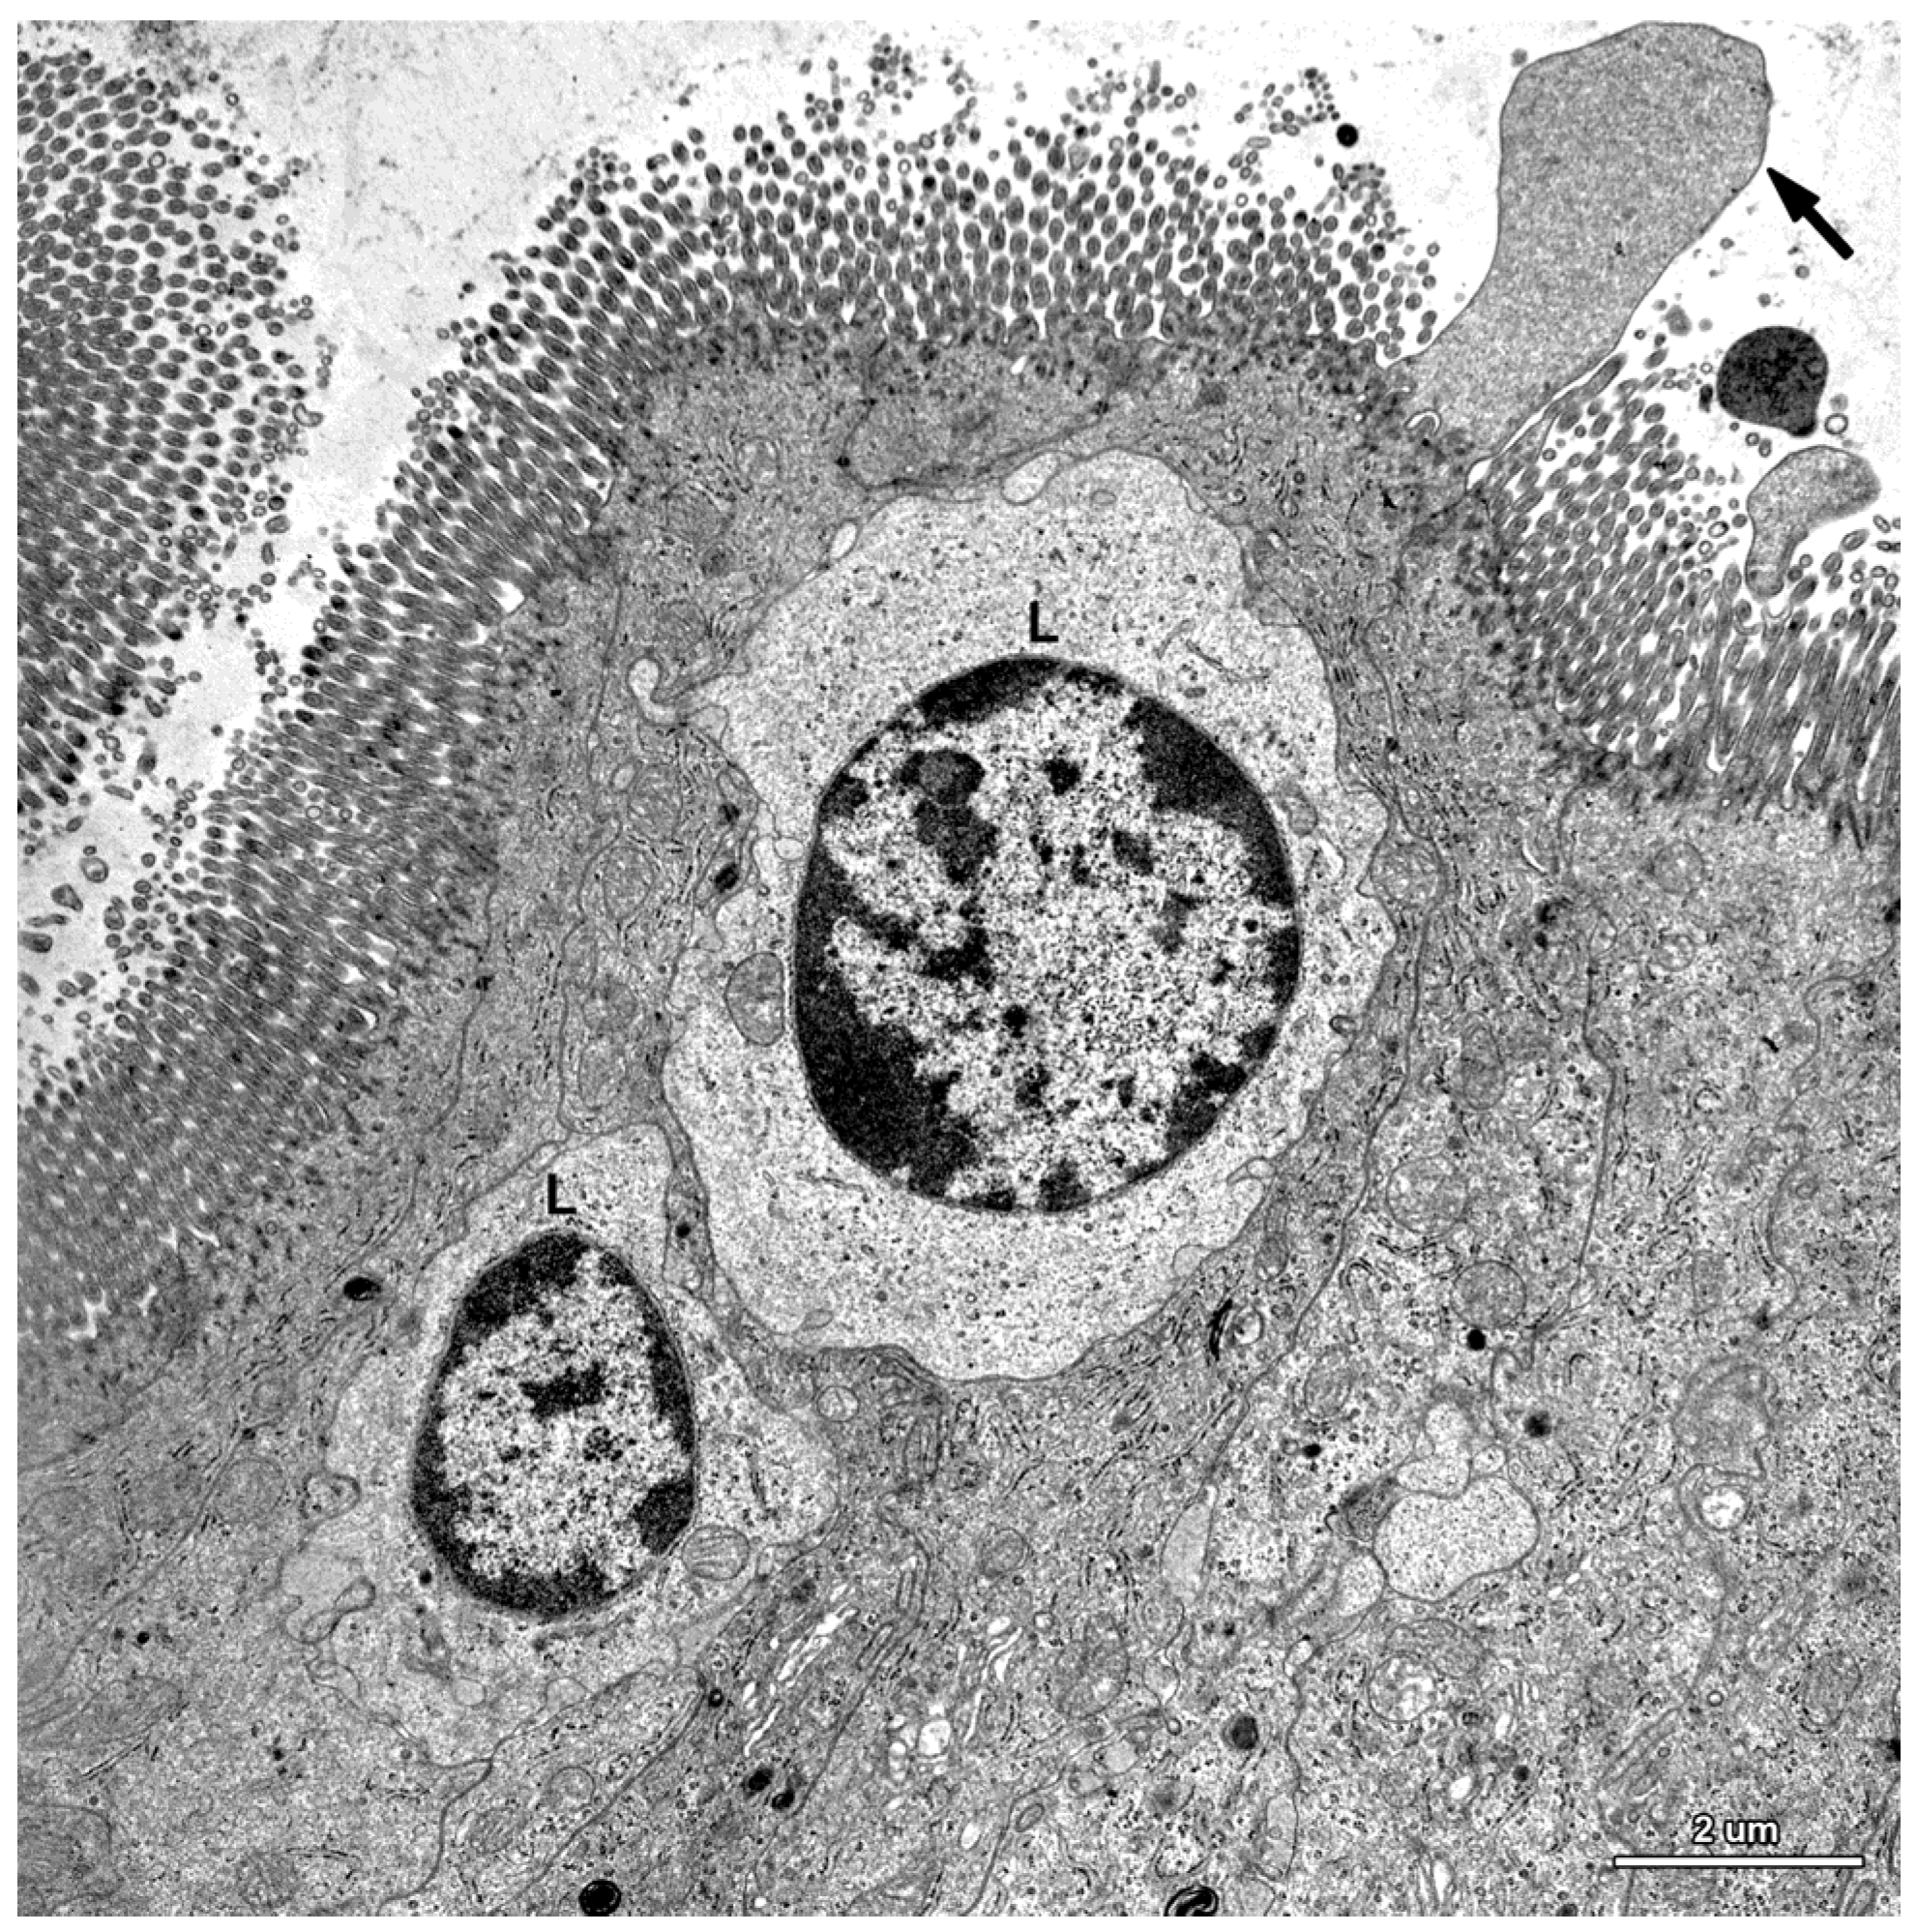

Figure 7.

Ultrastructure of the jejunal mucosal epithelium in a pig that received ZEN for one week. (A) Drop-like protrusions extending from the apical surface of the enterocytes; (B) Lymphocytes (L) between epithelial cells.

Figure 8.

Ultrastructure of the epithelium in a pig that received DON + ZEN for six weeks. Note the drop-like protrusion (arrow) extending from the apical surface of enterocyte and numerous lymphocytes (L) between the epithelial cells.

In this study, we paid special attention to the microvilli of the absorptive cells because on one hand, they are exposed to the highest levels of toxin and on the other hand, they play a crucial role in nutrient adsorption. In the samples taken from the control and mycotoxin-treated pigs, well-developed, parallel microvilli covered the entire apical surface of the enterocytes (Figure 6A). In the pigs receiving ZEN and DON + ZEN, adsorptive cells with drop-like protrusions of apical cytoplasm that affected the distribution of the microvilli were also noted (Figure 7A and Figure 8). These cells occurred infrequently but were found in all gilts treated with ZEN.

A characteristic feature of the epithelium covering the villi was the presence of numerous lymphocytes in samples taken from pigs that received ZEN for one week as well as ZEN, DON or DON + ZEN for three and six weeks (Figure 7, Figure 8 and Figure 9).